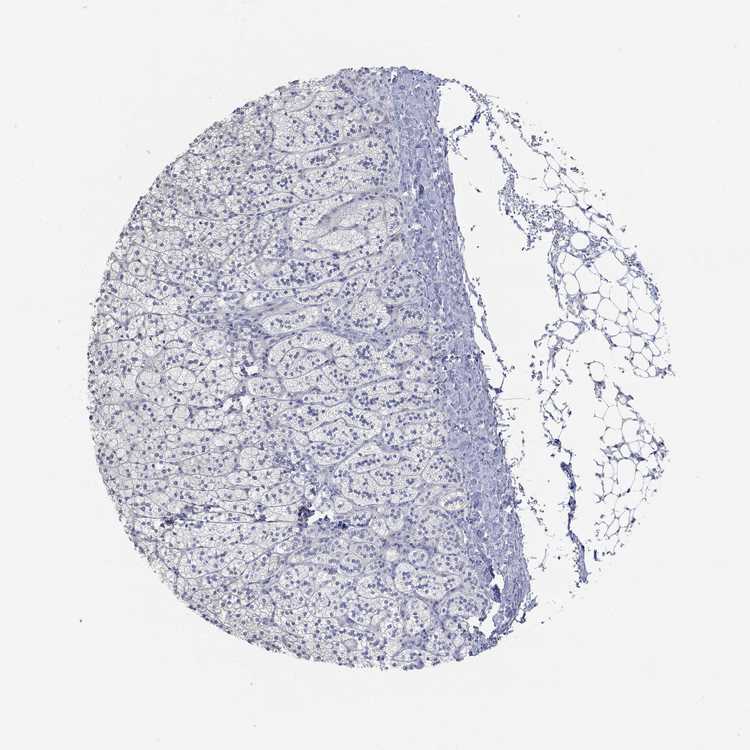

ADRENAL GLAND - Antibody stainingi

Antibody staining in the annotated cell types in the current human tissue is reported as not detected, low, medium, or high, based on conventional immunohistochemistry profiling in selected tissues. This score is based on the combination of the staining intensity and fraction of stained cells.

Each image is clickable and will lead to virtual microscopy that enables deeper exploration of all samples and also displays staining intensity scores, fraction scores and subcellular localization as well as patient and tissue information for each sample.

Antibody HPA039477

Glandular cells Not detected